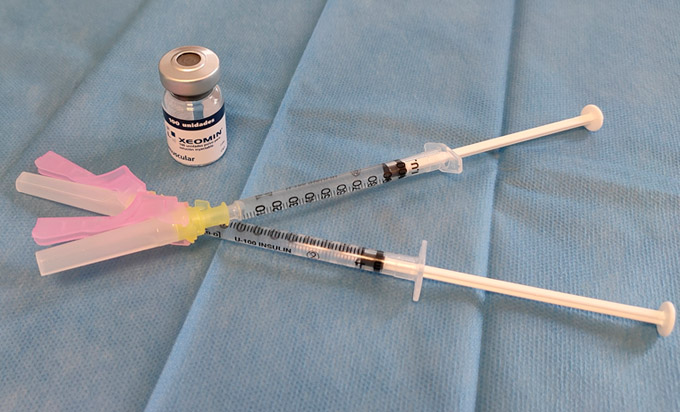

En muchas ocasiones, debido al estrés, apretamos los dientes sin darnos cuenta durante el día o la noche. Los principales signos y síntomas del bruxismo son el desgaste de nuestros dientes, los dolores mandibulares o de cabeza, la sensación de tensión muscular y los chasquidos de la articulación temporomandibular. Protege tus dientes y articulación con nosotros.

La sedación consciente es una técnica muy demandada en odontología y cirugía maxilofacial cuyo objetivo es mantener un estado de bienestar y tranquilidad, permitiendo realizar tratamientos de forma más cómoda y efectiva.

En la Clínica Dental José de Pedro contamos con el apoyo de médicos anestesistas para llevar a cabo los procedimientos bajo sedación consciente.